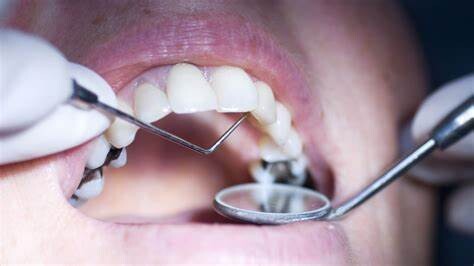

What should you do if you think you have a cavity? The first step is to see your dentist. Although cavities can be reversed in the early stages, by the time you are feeling discomfort or pain, only a dentist can treat them. An x-ray will be taken to determine how the cavity has progressed into the tooth. Depending on how severe the cavity is, you might need a filling to fix it. If the decay is very severe, the dentist might replace the tooth with a crown or perform a root canal.

Even if you're not sure if you have a cavity, regular professional cleaning and dental visits are important. A dental hygienist can apply a fluoride treatment to help strengthen the teeth and reverse the very early stages of decay. He or she can also give you tips on the best ways to brush your teeth and advise you about what foods to avoid or consume less frequently to reduce your risk for cavities. As with many conditions, when it comes to cavities, taking preventative steps is a lot easier than treating the problem down the road.